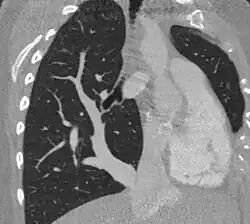

Scimitar syndrome chest CT

The diagnosis is made by transthoracic or transesophageal echocardiography and selective pulmonary angiography.[5] More recently by CT angiography or MR Angiography.

Pulmonary angiography demonstrates anomalous arterial supply to right lower lobe.[5]